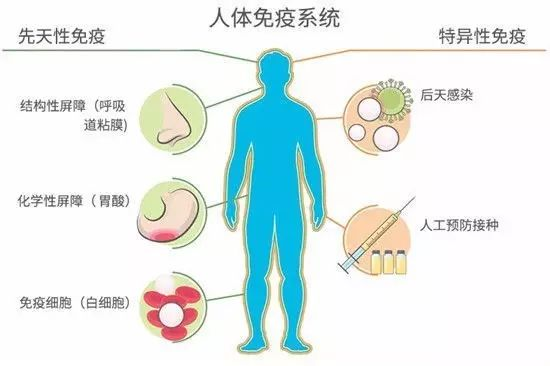

众所周知,我们每天都遭受各种病毒的频频轰炸。

水痘-带状疱疹病毒(VZV病毒)也总会不经意入侵到我们的身体内。

大多数情况下,人体的免疫系统会对它进行防御,保护我们不被其感染。

但总会有一些漏网之鱼的出现,让我们成为VZV病毒的携带者。

不过,这些悄悄潜伏在人体内的病毒固然可怕。但自它们入侵人类身体的那天起,人体内的免疫系统就不停的加班加点。它们不断逮捕病原体,制造抗体来保护身体的细胞。所以,就算病毒潜伏再久,免疫系统给力也不容易生病,而且好得快。

若是只要免疫能力稍微下降,潜伏在人体内的病毒就开始为所欲为了。可见,预防病毒感染和自愈疾病的根本是持续保持免疫系统的战斗力。其实做到这一点也不难,只要我们多呵护它们就行了。

比如最简单的方法就是保持良好的睡眠。这是因为我们体内的T细胞是负责对付癌细胞和病毒。若是得不到充足的睡眠,T细胞的数量就会减少,免疫系统就会下降,随之生病概率增加。此外,常做运动,也有利于我们增强免疫系统功能等。 不只是人类疱疹病毒这一大类,我们体内还可能长期潜伏着其他病毒或是致病细菌等。但它们的存在真的会对我们造成致命的威胁吗?其实不然。也许真正可怕的是人们根本不在乎,甚至去破坏体内那一辈子忠实保护自己的免疫大军。这样一来,那些致病因子又怎会对你手下留情呢?